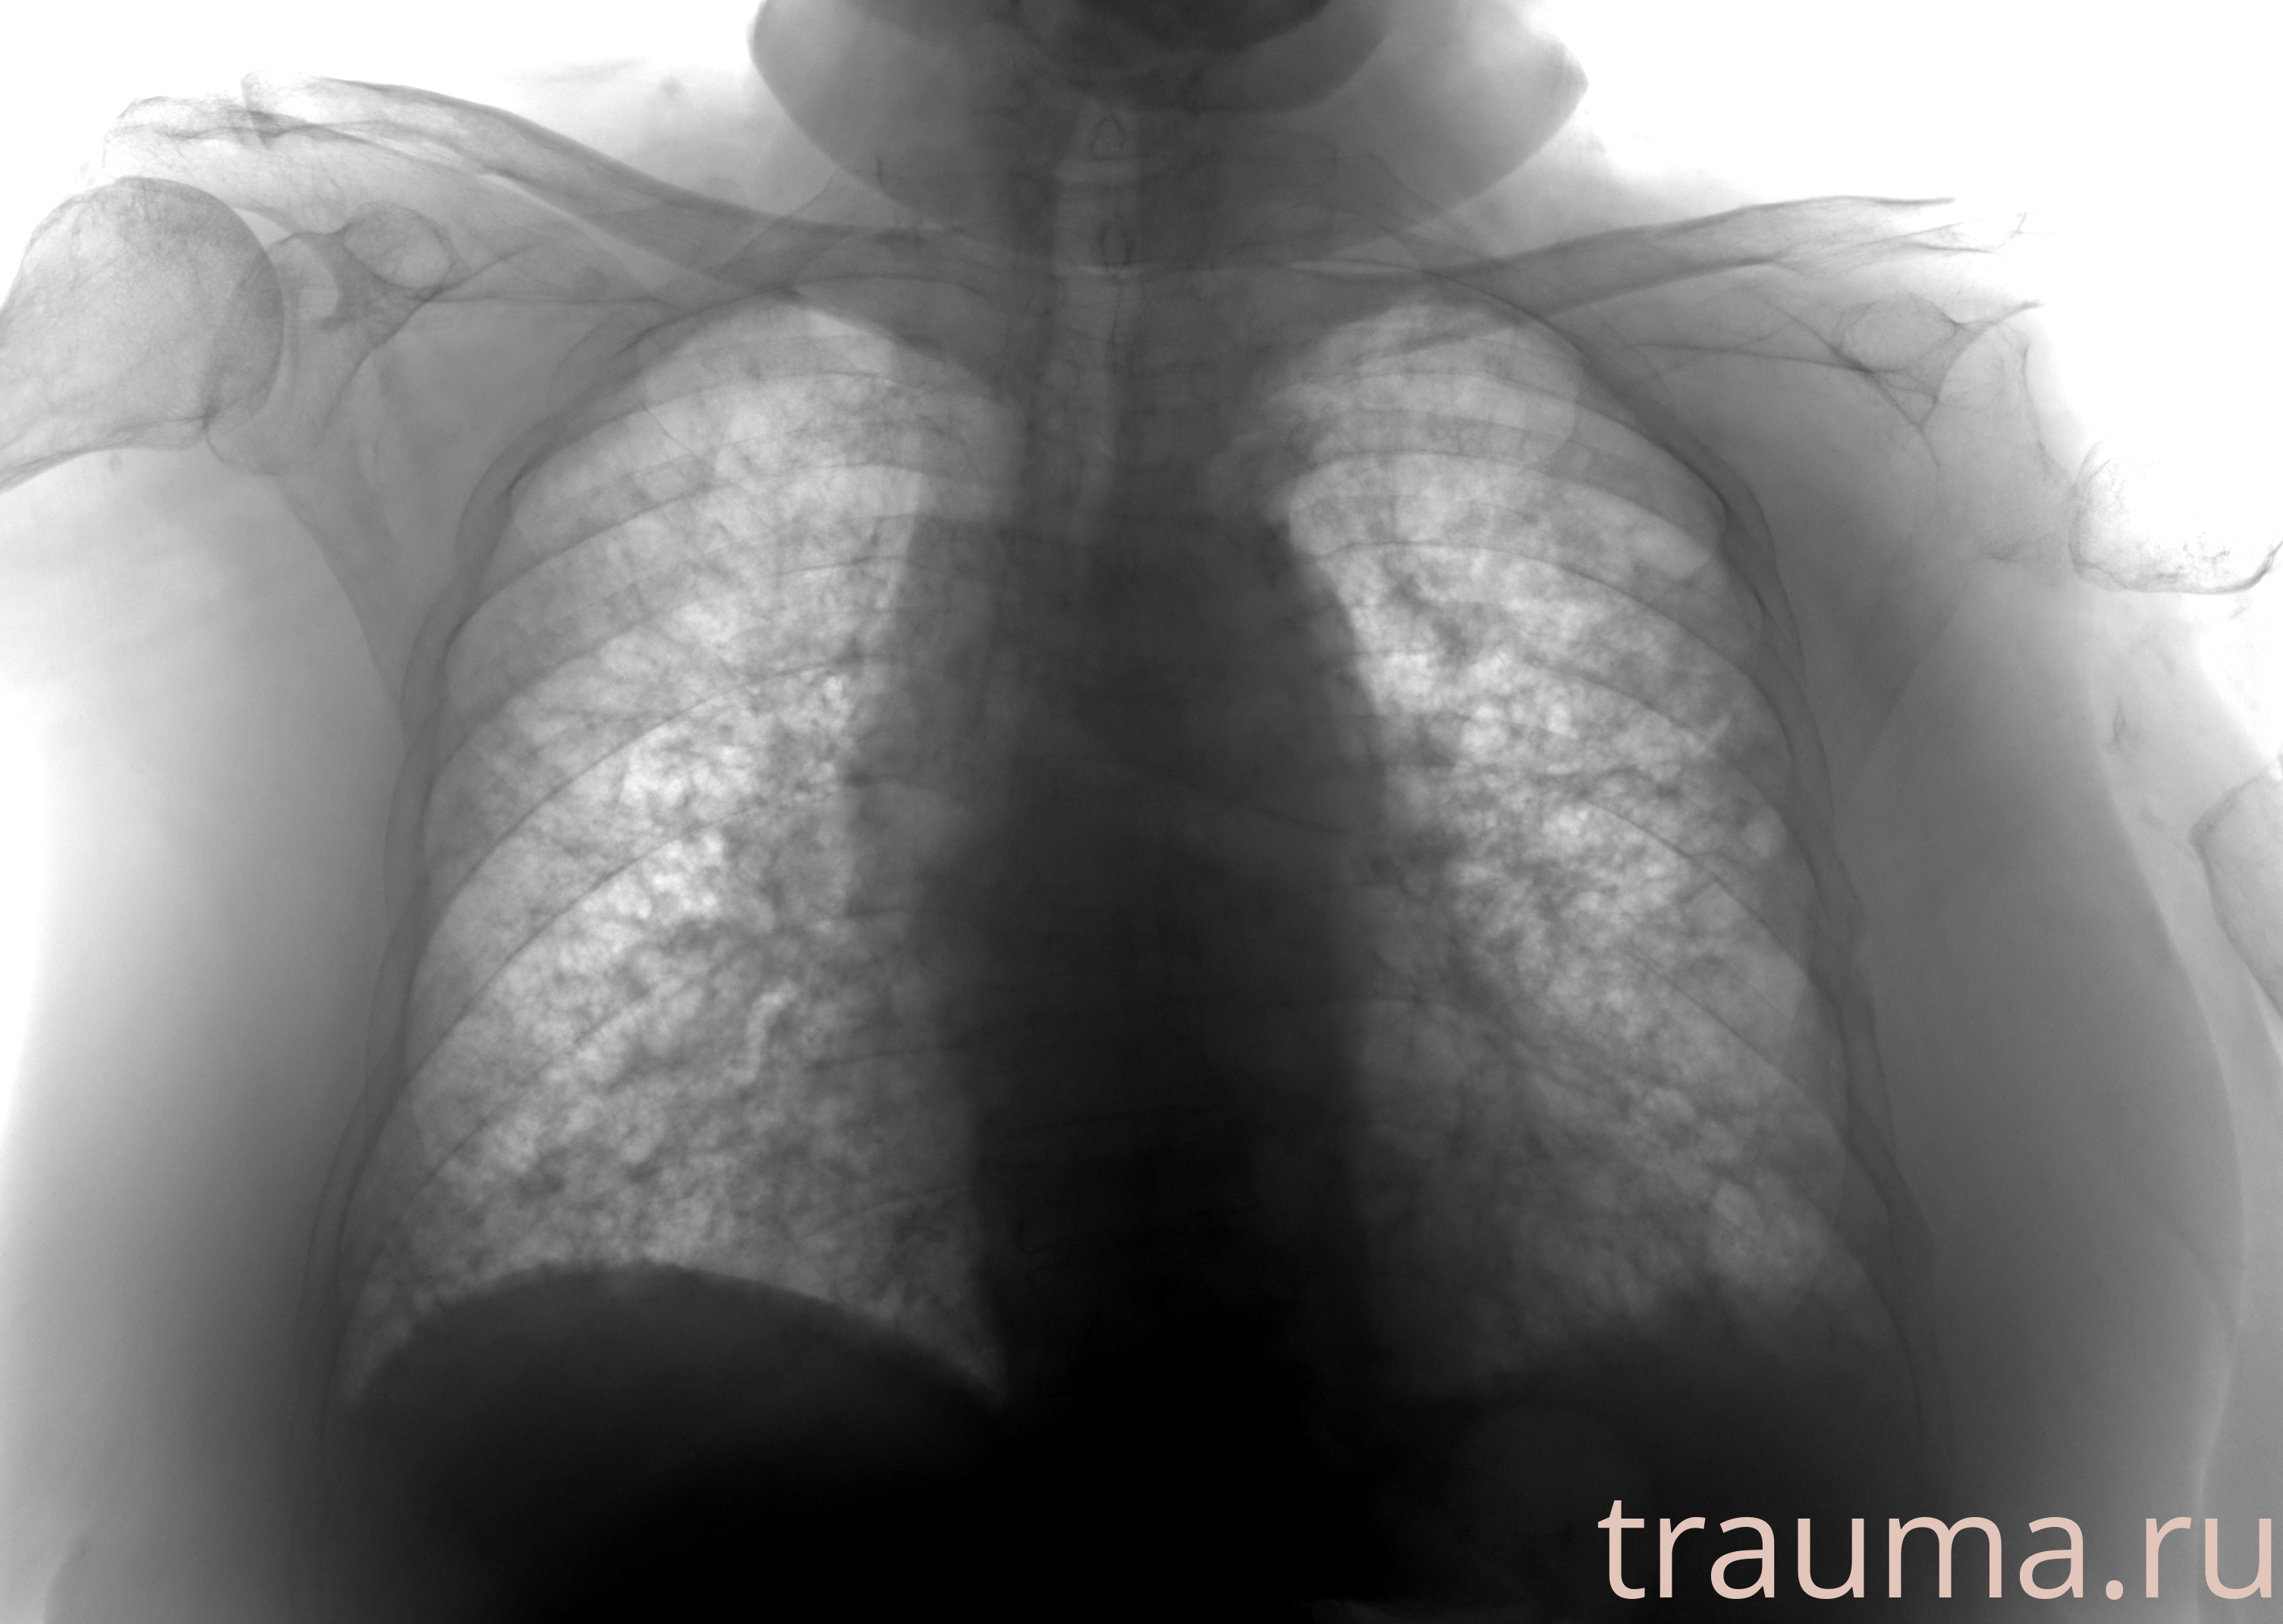

Рентгенограммы

Рентген на дому: по вашему адресу приезжает врач-рентгенолог, травматолог-ортопед с мобильным рентгеновским аппаратом, проводит диагностику травмы или заболевания, делает необходимые рентгенограммы, дает рекомендации по дальнейшему лечению. Получить качественные снимки в домашних условиях возможно благодаря уникальной методике, разработанной МосРентген Центром для института  Склифосовского

при переломе шейки бедра и пневмонии от компании МосРентген Центр - партнера Института имени Склифосовского